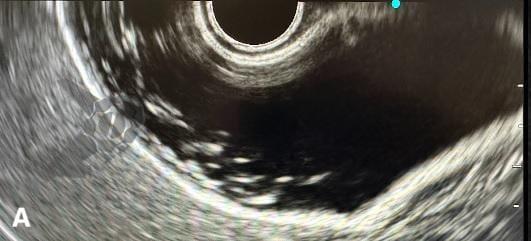

El polvo biliar se ha definido como una imagen hiperecoica flotante, sin sombra acústica posterior, observada o acentuada tras la palpación abdominal³. Se trata, por lo tanto, de la misma entidad ecográfica que, en Brasil, tradicionalmente se ha denominado “microlitiasis”, pero que no se ajusta a la definición de consenso internacional de microlitiasis y terminó siendo prácticamente ignorada por el consenso, o, en algunos casos, incluida a la fuerza bajo el término “lodo biliar”.

El polvo biliar se definió como una imagen hiperecoica flotante, sin sombra acústica posterior, observada o acentuada tras la palpación abdominal — una entidad ecográfica anteriormente denominada “microlitiasis” o “microcálculo” en nuestro medio. La introducción de este término busca conciliar los hallazgos ecográficos frecuentemente observados en la práctica diaria con las definiciones establecidas por el Consenso Internacional de 2023.